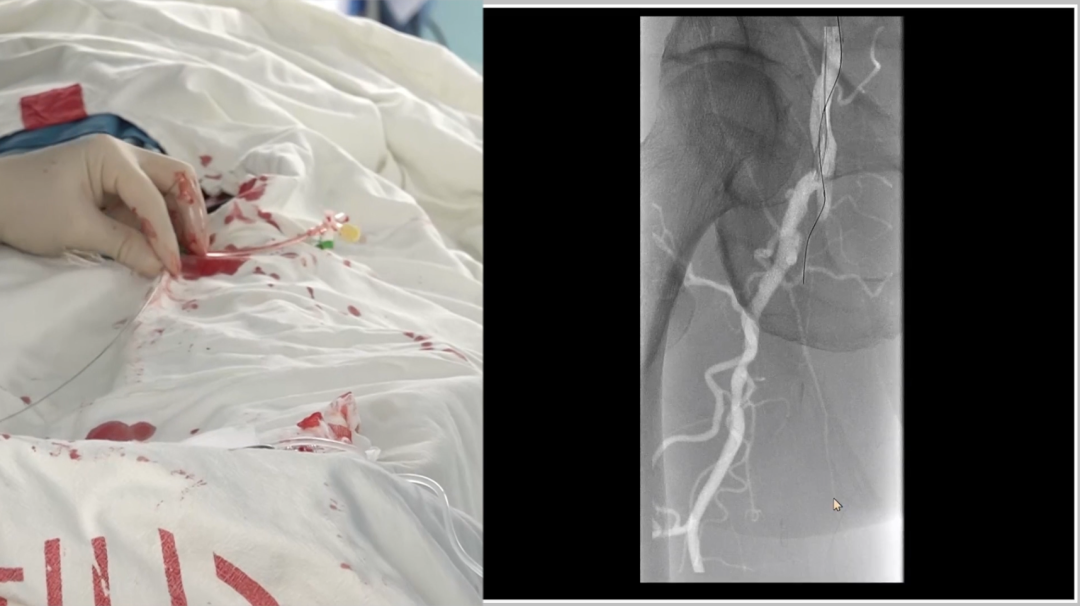

导丝突破:多种器械配合,应对坚硬病变

初始使用单弯导管配合Command18导丝尝试突破股动脉起始段纤维帽,未成功;

更换Terumo导丝后突破纤维帽,但支撑导管跟进困难,提示病变质地坚硬;

先后尝试Command 18、Treasure12 CTO导丝等,均难以顺利通过病变段;

关键技巧:采用"自制CTO导丝"——剪除V18导丝部分软头,塑形后利用其强支撑性,顺利通过病变并跟进支撑导管。